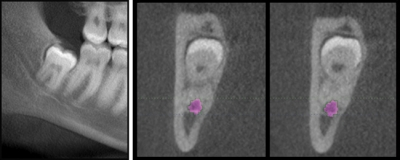

Dr. Lloyd Zivian's patient, 45-year-old Neal, had unusual symptoms on tooth No. 8. The periapical showed a small, distal radiolucency. With only 2-D X-rays to work with, Dr. Zivian would have had to do exploratory surgery, most likely sacrificing the buccal plate. The sagittal view of Neal's CBCT scan showed that the entire facial aspect of the root had resorbed, and the tooth was nonrestorable. Not only did the scan show the extent of the pathological area, it also showed that the buccal plate was intact - excellent prognosis for an implant. Since Neal and Dr. Zivian had a better idea what to expect prior to surgery, Neal was not as fearful consenting to a shorter and more productive surgery.